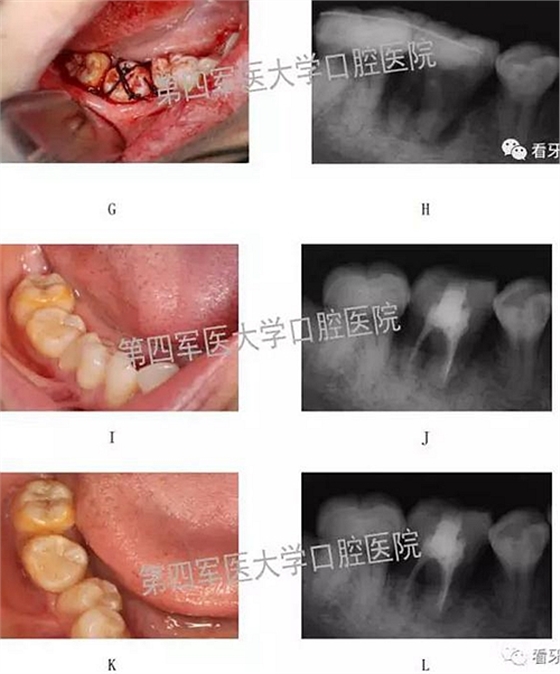

四、典型病例:

二,牙槽內(nèi)移植

1,阻生牙牽出再值